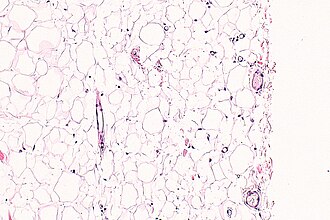

Mature adipose tissue (lipoma). H&E stain. | |

| LM | mature adipocytes |

- Collection of mature adipocytes.

- Variation of size may be seen -- should prompt a search for lipoblasts.[4]

- Microscopically not definitely distinguishable from mature clump of fat.

The sections show mature adipocytes. There is no increase in vascularity. No thick fibrous septa are present.